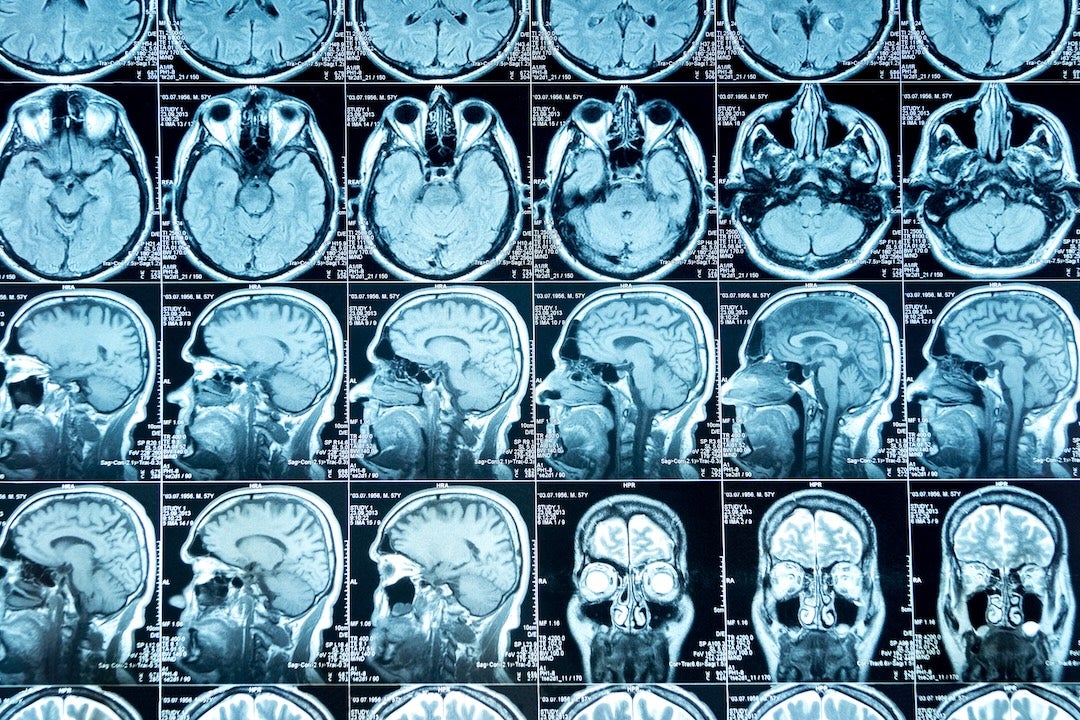

Deep sleep is essential for clearing waste products from the brain through the flow of cerebrospinal fluid. These nightly “cleaning cycles” help remove toxic proteins, such as amyloids, that accumulate during the day and are linked to Alzheimer’s disease and other dementias.

“Our goal is to measure and improve the brain’s ability to clear waste during deep sleep,” Aazhang said. “We are building a system that not only tracks the brain’s clearing process but can also stimulate it, improving natural mechanisms that protect against neurodegeneration.”